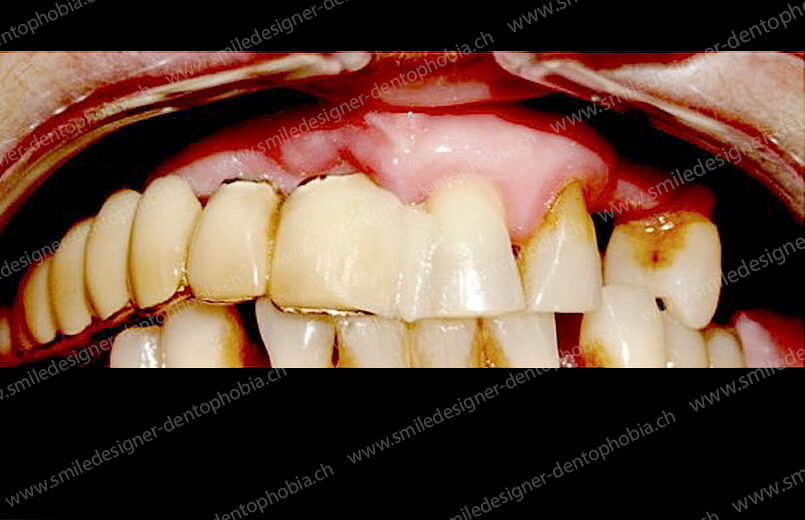

Cas clinique « GOLD STANDARD MCI » bi-maxillaire : Bridge implanto-porté sans extension postérieure (ALL ON 10). Version définitive des bridges avec un cosmétique en céramique.

Cas clinique « GOLD STANDARD MCI » bi-maxillaire : Bridge implanto-porté sans extension (ALL ON 8) au maxillaire et à la mandibule. Version définitive des bridges avec un cosmétique en céramique.

Cas clinique « GOLD STANDARD MCI » maxillaire : Bridge implanto-porté sans extension (ALL ON 8). Version définitive des bridges avec un cosmétique en céramique.

Cas clinique « GOLD STANDARD MCI » maxillaire : Bridge implanto-porté sans extension (ALL ON 10). Version définitive des bridges avec un cosmétique en céramique.

Cas clinique « GOLD STANDARD MCI » bi-maxillaire : Bridge implanto-porté sans extension (ALL ON 10). Version définitive des bridges avec un cosmétique en céramique.

Cas clinique « GOLD STANDARD MCI » bi-maxillaire : Bridge implanto-porté sans extension (ALL ON 8). Version définitive des bridges avec un cosmétique en céramique.